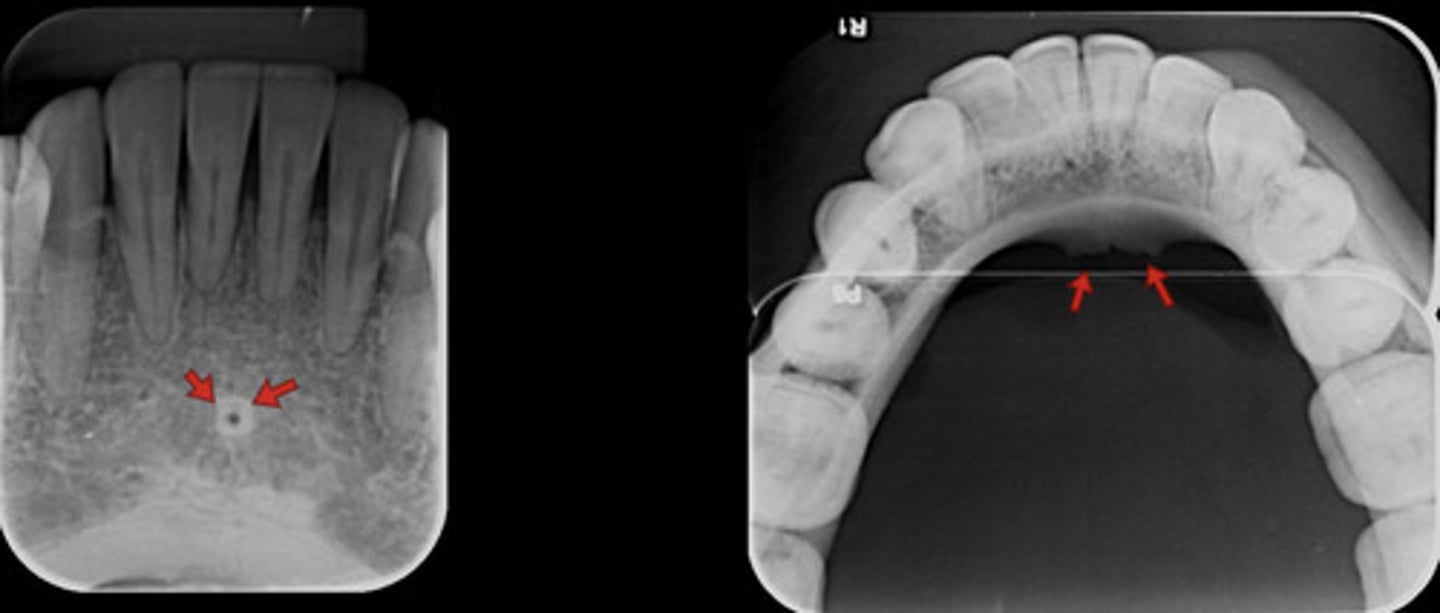

What is the lingual foramen?

What does the lingual foramen look like radiographically?

INFOrmation on lingual foramen

radiolucent & in the mandible srrouned on genial tubercules

What are genial tubercles?

information genial tubercules

inferior to mandibular incisors & radiopaque

What do genial tubercles look like radiographically?